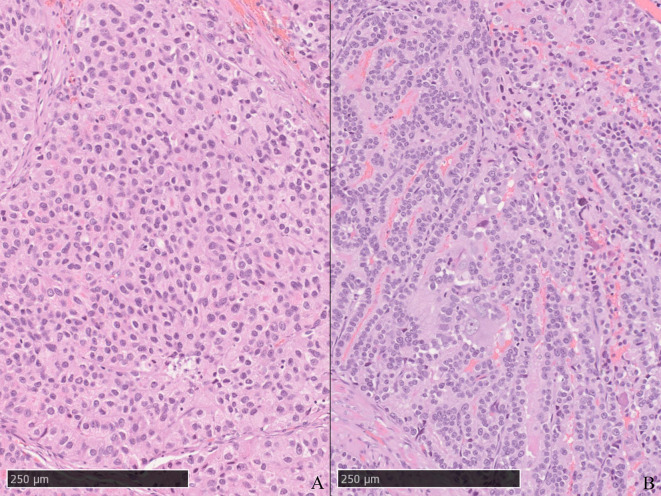

本文报告一例22岁雄性松鼠猴患原发性精囊腺癌(PSVA)。动物表现为血尿和消瘦。精囊肿瘤的病理解剖显示一个形状不规则的白色实性肿块,显示导管/乳头状和实性形态,导管内有周期性的酸-希夫阳性粘液。小泡因血液而扩张。肿瘤细胞呈细胞质嗜酸性颗粒,向肿瘤组织过渡。免疫组化分析显示所有肿瘤细胞角蛋白均为阴性;只有导管/乳头状细胞呈vimentin阳性。其他器官无肿瘤。PSVA的诊断基于肿瘤起源部位和组织病理学,类似于实验室啮齿动物的PSVA。本研究报告了一例新世界猴的PSVA。

This report presents the case of a 22-year-old male squirrel monkey with primary seminal vesicle adenocarcinoma (PSVA). The animal presented with hematuria and emaciation. Pathological autopsy of the seminal vesicle tumor revealed an irregularly shaped, white, solid mass showing ductal/papillary and solid patterns and periodic acid-Schiff-positive mucus in the duct. The vesicle was dilated by blood. Tumor cells showed cytoplasmic eosinophilic granules, and a transition to tumor tissue was observed. Immunohistochemical analysis indicated that all tumor cells were cytokeratin-negative; only ductal/papillary cells were vimentin-positive. Other organs were tumor free. PSVA was diagnosed based on the site of tumor origin and histopathology, similar to PSVA in laboratory rodents. This study reports a case of PSVA in a new-world monkey.